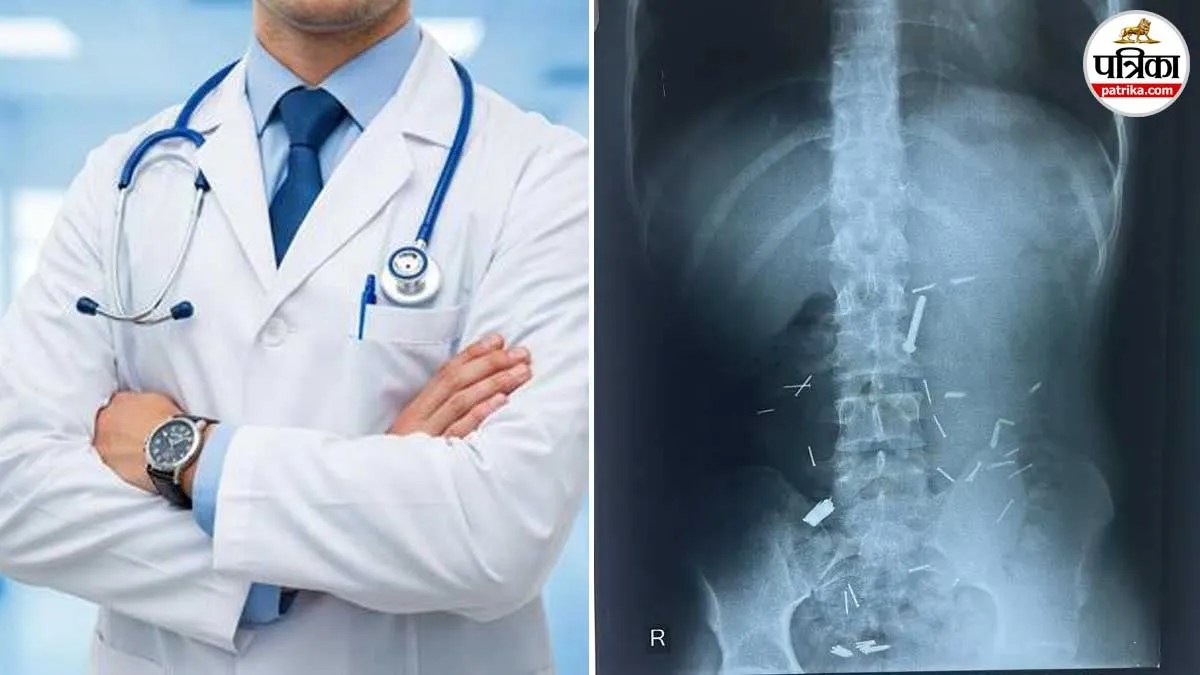

अस्पताल में प्राथमिक जांच और एक्स-रे रिपोर्ट सामने आने के बाद डॉक्टर भी चौंक गए। युवक के पेट के अंदर बड़ी संख्या में कीलें साफ दिखाई दे रही थीं। इतनी अधिक और नुकीली वस्तुओं का शरीर में होना बेहद खतरनाक स्थिति थी, जिससे आंतों को गंभीर नुकसान पहुंच सकता था।

गैस्ट्रो सर्जन के नेतृत्व में विशेषज्ञों की टीम ने युवक का ऑपरेशन शुरू किया। करीब पांच घंटे तक चले इस जटिल ऑपरेशन में एंडोस्कोपी, सर्जिकल तकनीक और सी-आर्म इमेजिंग मशीन की मदद से एक-एक कर सभी कीलों को निकाला गया। यह प्रक्रिया बेहद जोखिमपूर्ण और चुनौतीपूर्ण थी।

डॉक्टरों के अनुसार, कीलें छोटी और बड़ी आंत में अलग-अलग स्थानों पर फैल चुकी थीं। कई जगहों पर उन्होंने आंतों में पंक्चर भी कर दिया था, जिससे स्थिति और अधिक गंभीर हो गई थी। हर कील को सुरक्षित तरीके से निकालना डॉक्टरों के लिए बड़ी चुनौती थी।